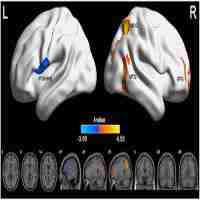

| Description | Journal: Brain and Behavior Neuroimaging studies can shed light on the neurobiological underpinnings of autism spectrum disorders (ASD). Studies of the resting brain have shown both altered baseline metabolism from PET/SPECT and altered functional connectivity (FC) of intrinsic brain networks based on resting-state fMRI. To date, however, no study has investigated these two physiological parameters of resting brain function jointly, or explored the relationship between these measures and ASD symptom severity. Here, we used pseudo-continuous arterial spin labeling with 3D background-suppressed GRASE to assess resting cerebral blood flow (CBF) and FC in 17 youth with ASD and 22 matched typically developing (TD) children. A pattern of altered resting perfusion was found in ASD versus TD children including frontotemporal hyperperfusion and hypoperfusion in the dorsal anterior cingulate cortex. We found increased local FC in the anterior module of the default mode network (DMN) accompanied by decreased CBF in the same area. In our cohort, both alterations were associated with greater social impairments as assessed with the Social Responsiveness Scale (SRS-total T scores). While FC was correlated with CBF in TD children, this association between FC and baseline perfusion was disrupted in children with ASD. Furthermore, there was reduced long-range FC between anterior and posterior modules of the DMN in children with ASD. Taken together, the findings of this study – the first to jointly assess resting CBF and FC in ASD – highlight new avenues for identifying novel imaging markers of ASD symptomatology. |